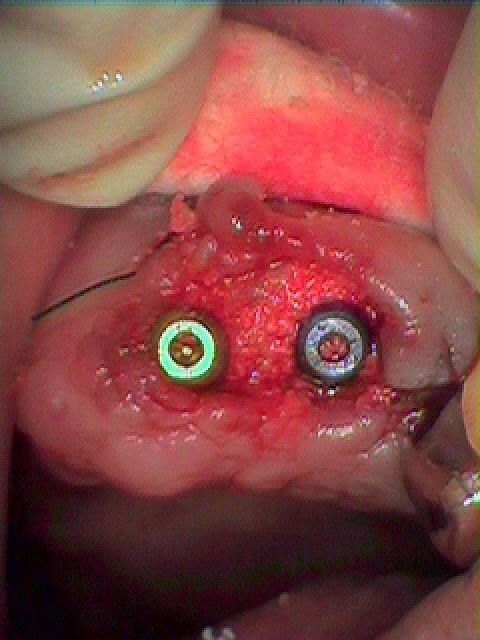

左上2,3番は虫歯も進行しており、抜歯してインプラントとなりました

インプラント埋入時になります

2番は3.25mmの13mmというインプラントを埋入しています

3番は4,0mmの13mmというインプラントを埋入しています

2番部はこのようにインプラントを適正な位置に即時埋入しています